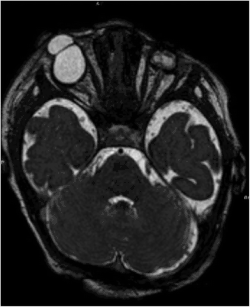

| Bilateral cryptophthalmos with microphthalmos in the left ocular globe and abnormal right ocular globe in a female infant with Fraser syndrome. | |

It is characterized by developmental defects including cryptophthalmos (where the eyelids fail to separate in each eye), and intersex development in the genitals (such as micropenis or clitoromegaly) and cryptorchidism.[3] Congenital malformations of the nose, ears, larynx and renal system, as well as developmental delays, manifest occasionally.[4] Syndactyly (fused fingers or toes) has also been noted.[5]